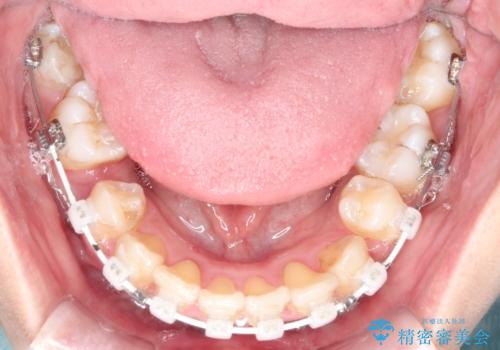

- ハーフリンガル

目立たないワイヤー矯正を希望されたので、上下左右のはを1本ずつ抜歯して、ハーフリンガル(上顎だけ裏側)にて矯正をすることにしました。

裏側装置の場合、歯磨きが難しいのと、慣れるまでは話しにくさや、違和感があります。

慣れてからは、とくに不自由さは感じない方が多いです。